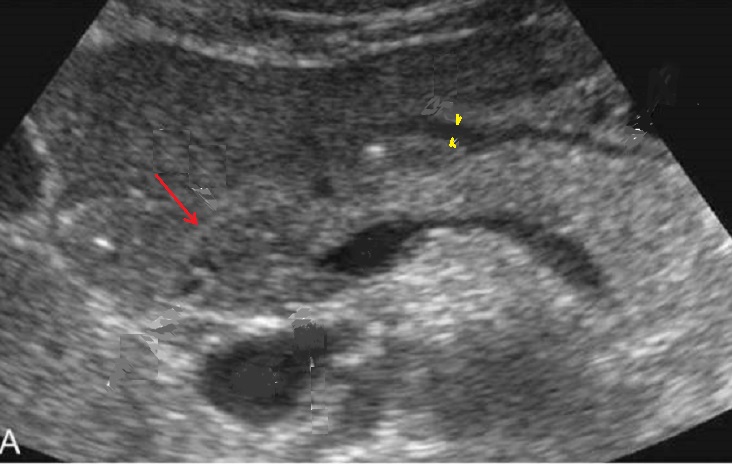

Image radiologique d'une

adenocarcinoma de la tete du pancreas ( fleche rouge

)avec signe indirect de dilatation du CPP et image

de pseudo-kyste a hypodense au queue du pancreas (

fleche jaune ) . Coupe TDM plus C+ axiale |